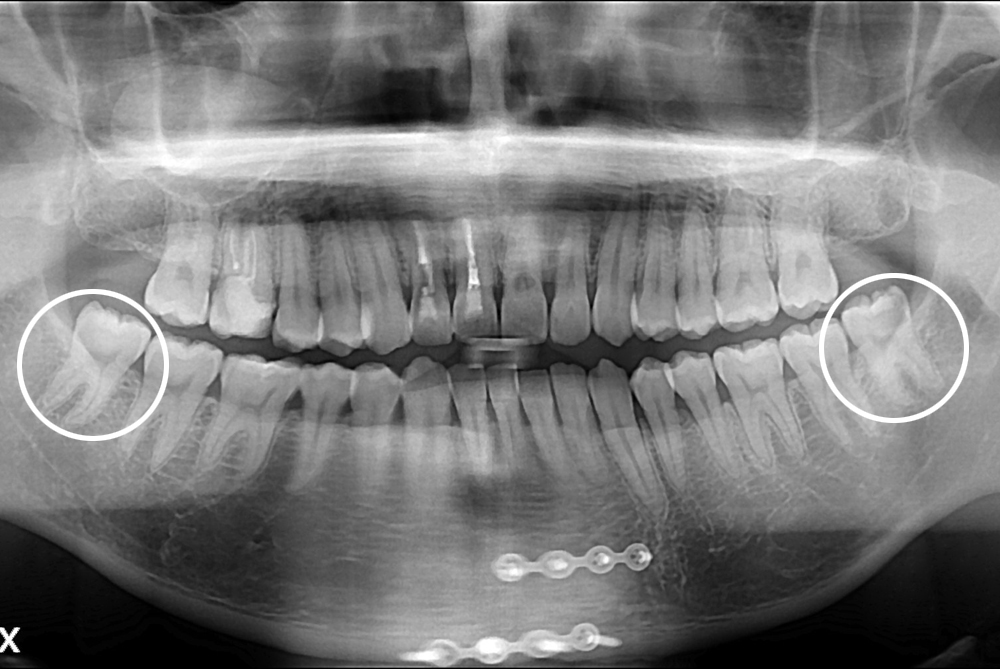

치료사례

세종치과의 진심 어린 치료는 결과로 말합니다.

실제 내원하신 환자분들의 치료 전·후 사례를 확인해보세요.

모든 치료사례 전후사진은 환자분의 동의하에 촬영되었습니다.

모든사진은 동일 환자분의 전후모습을 촬영하였으며, 사진의 밝기조절 외에 임의 수정이 없음을 알려드립니다.